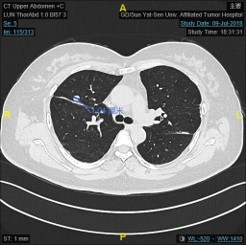

初诊 左肺转移消融后

右肺转移消融

2018.7.16于我院介入科再次行肺肿瘤微波消融术

右肺转移消融前: